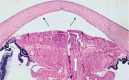

Peters plus syndrome is a rare congenital disorder that includes ocular anterior segment defects of the classic Peter's anomaly, and is mostly associated with craniofacial and skeletal defects. A 21-week fetus was referred for further evaluation due to a suspicion of fetal hydrocephalus. An ultrasound examination revealed hyperechogenic lenses, microphthalmia, hypotelorism, retrognathia, mild ventriculomegaly, absence of the cavum septum pellucidum, and short stature. Amniocentesis and further microarray analysis revealed normal chromosomal copy numbers including the gene B3GALTL. In utero mort fetalis occurred at the 23rd gestational week. Ultrasound and fetal autopsy findings were suggestive of Peters plus syndrome, but the absence of the B3GALTL gene mutation made the diagnosis Peters plus-like syndrome. Obstetricians should consider Peters plus-like syndrome with prenatal detection of ocular anomalies along with craniofacial and skeletal anomalies with the absence of B3GALTL gene mutation.